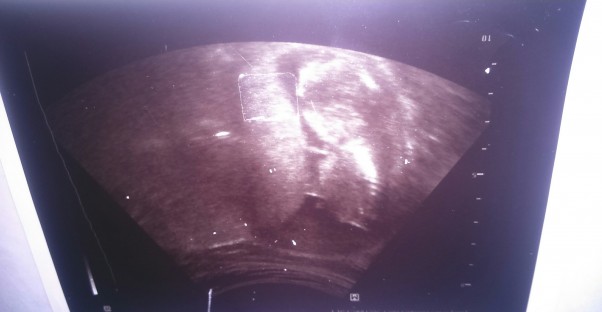

Zdjęcie nie wyraźne przez mój szwankujacy aparat fotograficzny. przewidywany termin z badania usg to 8 marzec